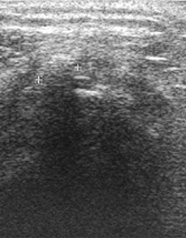

Abb 1; Ultraschall-Bild einer Rotatorenmanschettenruptur

Der Ultraschall ist für die Diagnosestellung in der Orthopädie unverzichtbar geworden. Die Untersuchung ist völlig schmerzfrei und bleibt ohne Nebenwirkungen. Anhand dieser Untersuchung lassen sich sehr gut Weichteilstrukturen beurteilen, die auf einem normalen Röntgenbild nicht sichtbar sind.

Dazu zählen unter anderem Weichteilveränderungen wie Verletzungen, Abnützungserscheinungen und Gelenkergüsse erkennen. Dadurch können wichtige Zusatzinformationen z.B. zum Röntgenbild gewonnen werden.

Im Schulterbereich können mittels Ultraschall eventuelle Verkalkungen im Sehnenbereich besonders leicht dargestellt und diagnostiziert werden (Kalkschulter).

Am Beispiel des Bildes links kann ein Spezialist z.B. eine Rotatorenmanschettenruptur an der Schulter erkennen (Abb 1).